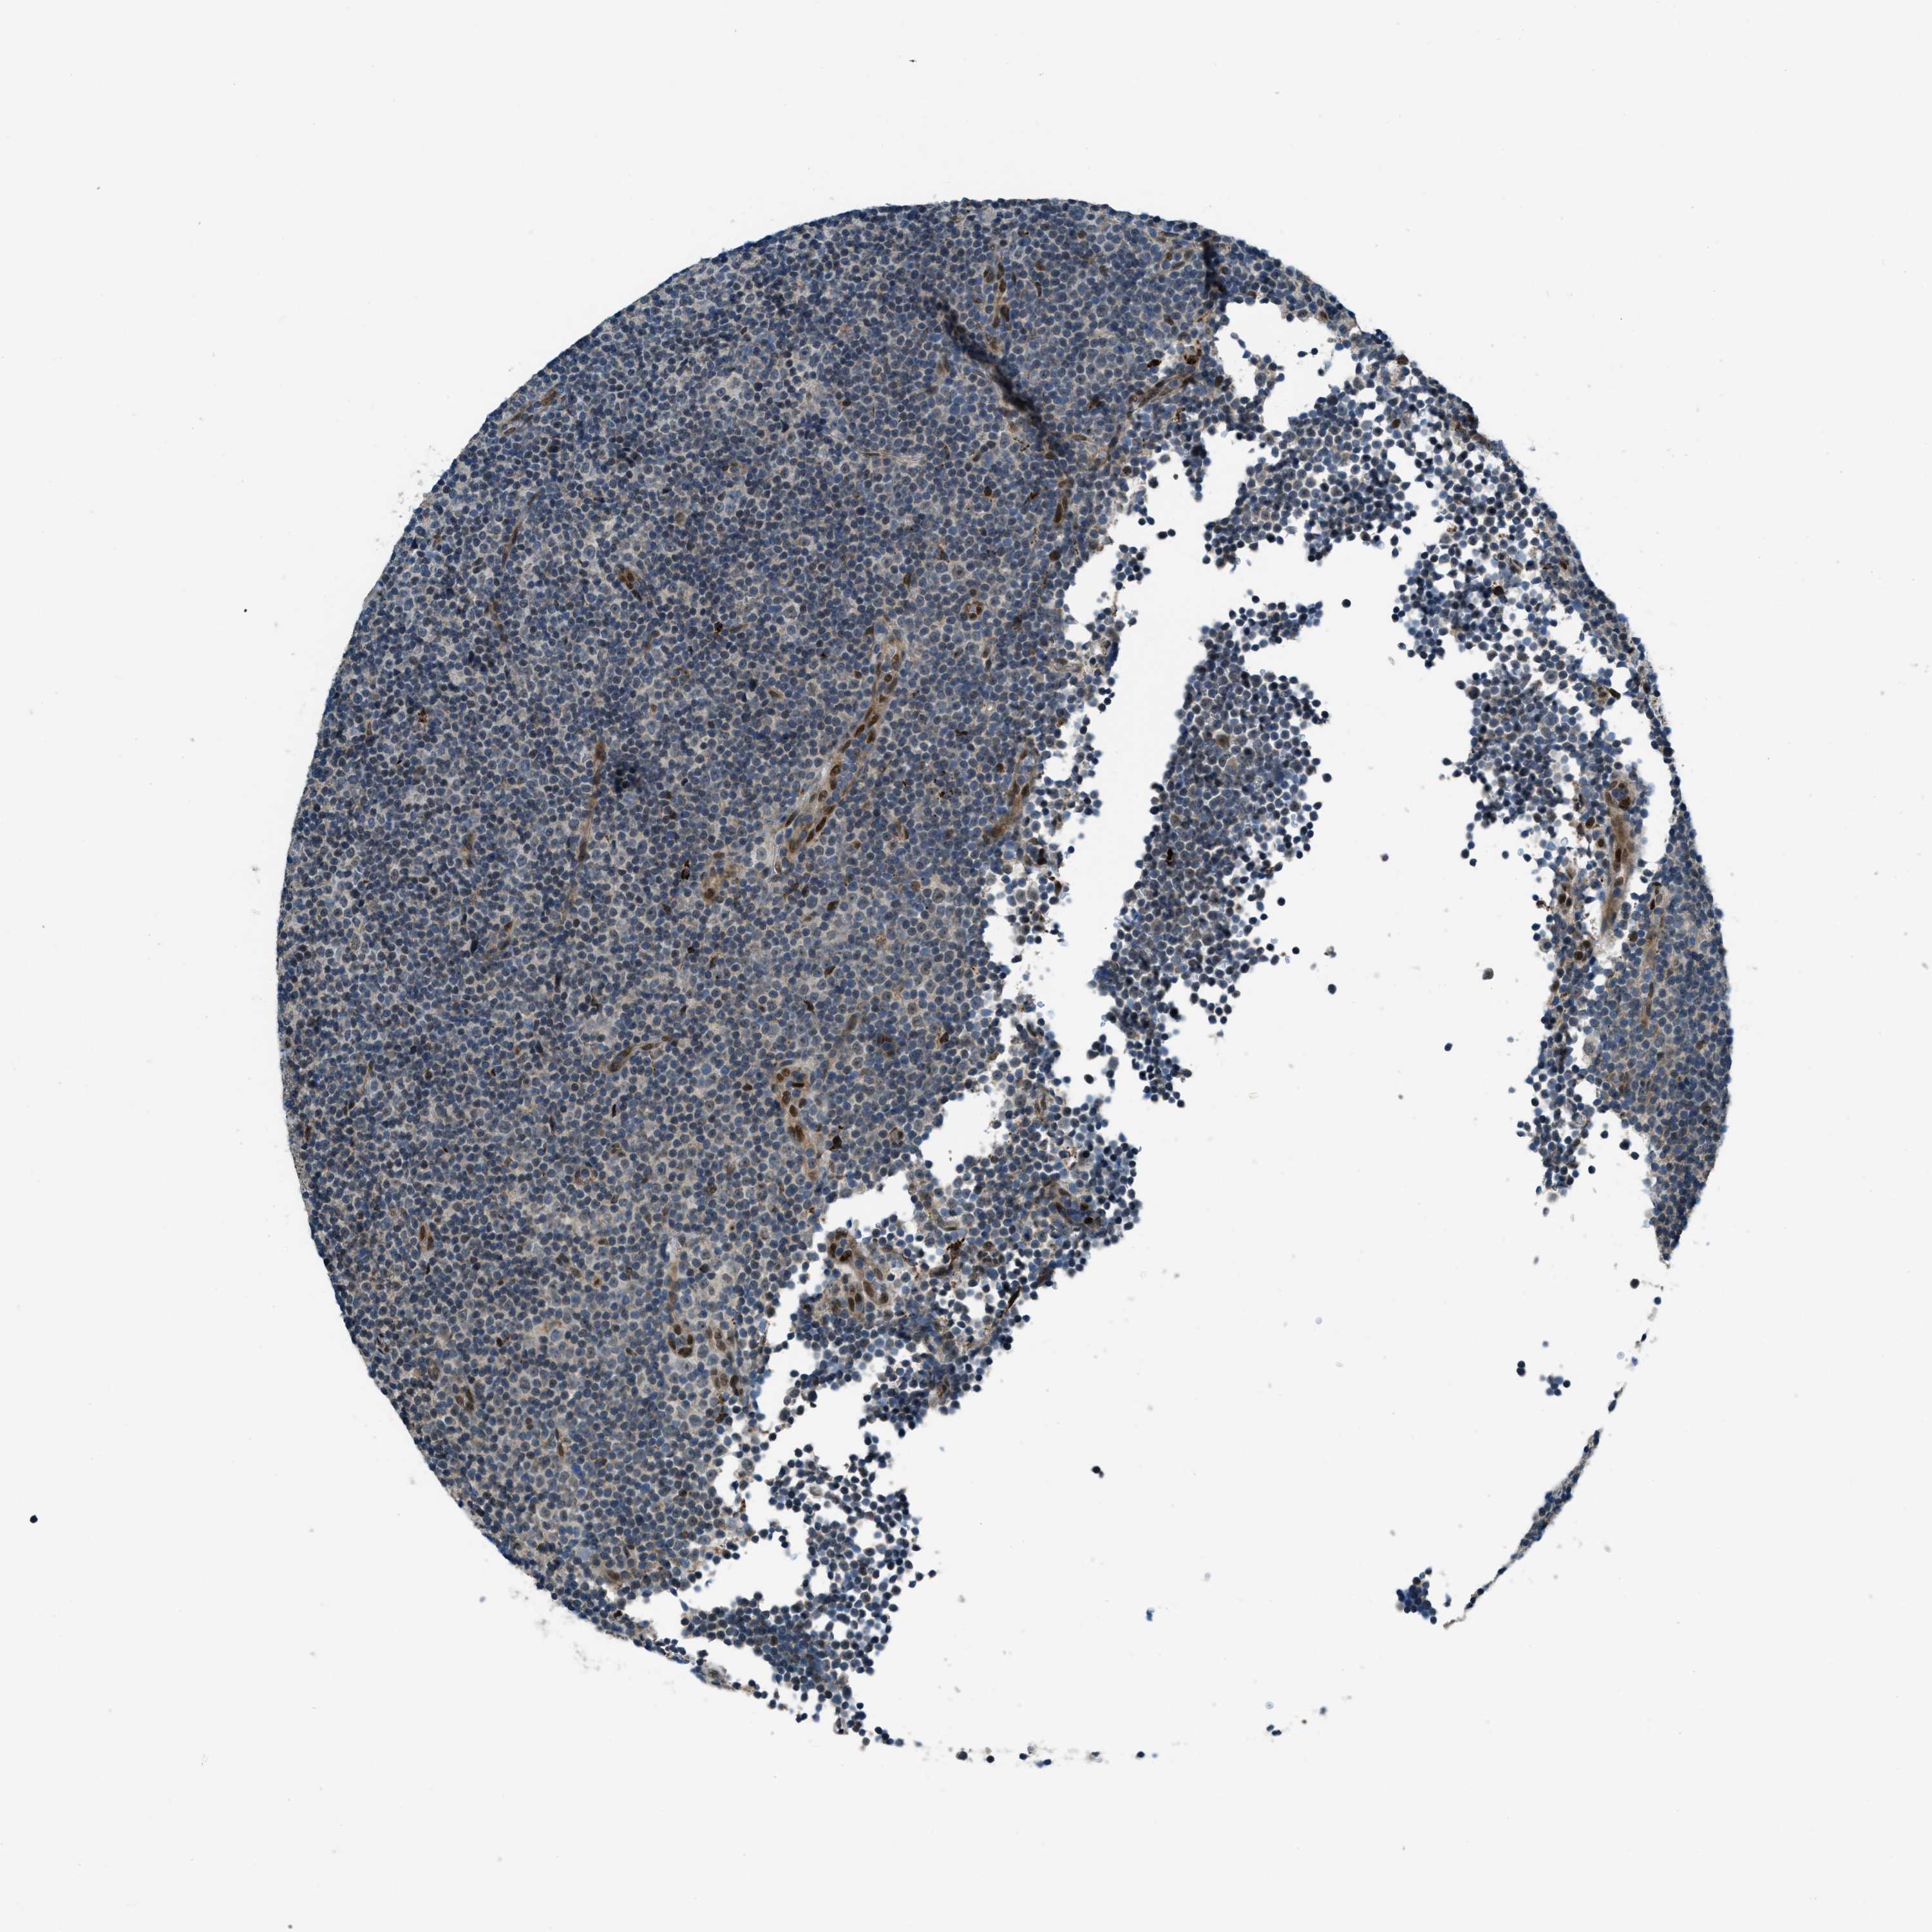

CANCER LYMPHOMA Show tissue menu

LYMPHOMA - Protein expressioni

A mouse-over function shows sample information and annotation data. Click on an image to view it in a full screen mode. Samples can be filtered based on level of antibody staining by selecting one or several of the following categories: high, medium, low and not detected. The assay and annotation is described here.

Each image is clickable and will lead to virtual microscopy that enables deeper exploration of all samples and also displays staining intensity scores, fraction scores and subcellular localization as well as patient and tissue information for each sample.

Antibody HPA036356

Antibody CAB004986

Antibody CAB017025

Hodgkin's disease, NOS

Malignant lymphoma, non-Hodgkin's type, High grade

Malignant lymphoma, non-Hodgkin's type, Low grade